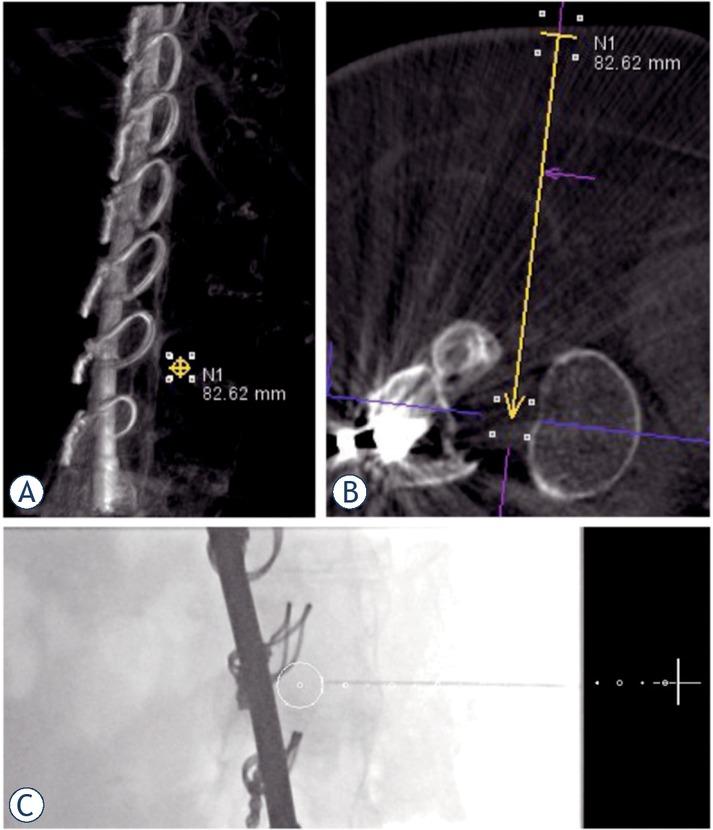

Integrated laser of the C-arm marked the entry position of the needle on the skin. The target point position was visualized under intermittent fluoroscopic guidance using two orthogonal views (Figures 1, 2, 3). Once the needle tip reached the target point, an aspiration of cerebrospinal fluid (CSF) was performed to confirm the intrathecal position. Afterwards, 5 ml of CSF was aspirated, and 5 ml nusinersen solution was intrathecally delivered according to the manufacturer’s instructions. After the procedure the patients were surveilled for 4-6 hours before being discharged.

(A). A 22-year-old female with severe scoliotic deformity of the spine; (B). The nusinersen administration was performed with interlaminar approach under cone-beam CT -guidance; (C). Introduction of the needle following the planned trajectory (white dotted line) to the target point (white circle).

(A). A 42-year old female after corrective surgery for scoliosis; (B). Transforaminal approach planning before needle introduction (yellow arrow); (C). Introduction of the needle following the planned trajectory (white dotted line) to the target position (white circle).